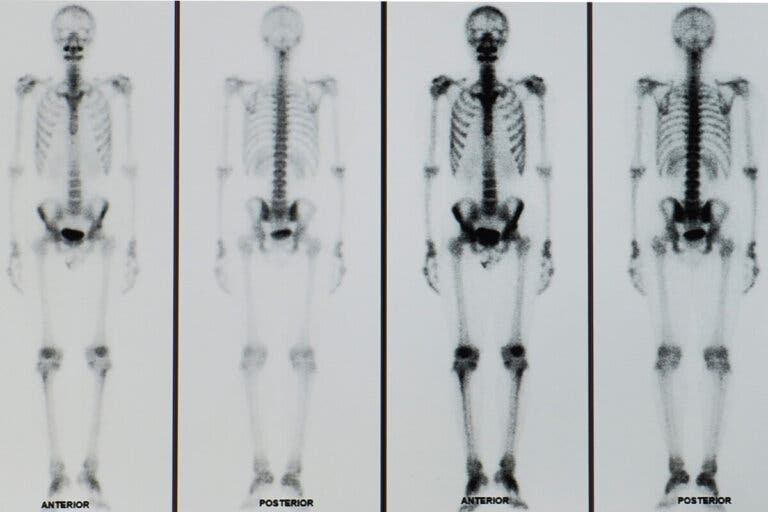

Los resultados de una gammagrafía ósea suelen estar listos en poco tiempo y deben ser analizados por un médico especialista. La sustancia marcadora se debe esparcir de forma uniforme en los huesos que no presentan ningún tipo de alteración.

Por otro lado, las zonas con una alteración en las células óseas presentan alteraciones en la captación. En este sentido, es posible observar zonas más claras o más oscuras que en el resto de los huesos.